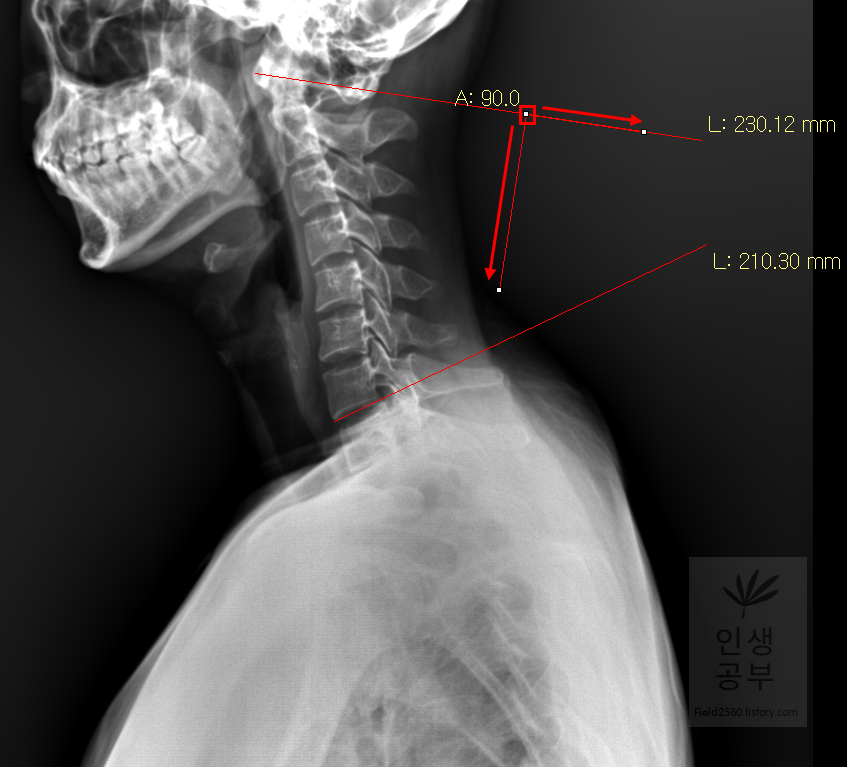

두 선사이에 수직인 선을 그어야 하기 때문에 각도기 모양이 있는 버튼을 눌러줍니다.

위쪽 선을 따라서 선을 긋고 90도를 맞춰서 선을 그어줍니다. 동그라미 표시된 곳을 먼저 찍어주고, 화살표를 따라서 위쪽 선을 따라서 그려주고, 90도 방향에 맞춰서 아래로 그어줍니다. 노란색 글자와 숫자가 아래줄 맞춰 준 곳에 있는데 A는 Angle 각도이고 옆에 있는 숫자가 현재 긋고 있는 각도의 값입니다

아래 선을 따라서 선을 긋고 90도에 맞춰서 선을 그어줍니다. 동그라미 표시된 곳을 먼저 찍어주고, 화살표를 따라서 아래쪽 선을 따라서 그려주고 90도 방향에 맞춰서 위로 그어줍니다. 위쪽 선에서 그은 선과 교차되게 그어주시면 됩니다.

두 선이 교차된 곳에서 각도가 생기게 됩니다. 이 각도를 Cobb 각이라고 합니다. 위쪽에 각도를 재거나 아래쪽에 각도를 재어도 똑같으니 원하는 방향의 각도를 측정해 주시면 됩니다. 각도를 측정할 때에는 두선이 교차한 곳에 먼저 클릭해주고 위 화살표 방향대로 오른쪽 왼쪽의 교차한 선을 따라서 측정해 주시면 됩니다. 왼쪽선을 먼저 그어도 되고 오른쪽 선을 먼저 그어도 상관없습니다.

위쪽에 있는 선은 첫 번째 목뼈(C1) 선을 그리기 위해 제일 튀어나온 앞쪽 부분 가운데 지점에(Center of Anterior arch)에서 시작해서 후궁(Posterior arch) 제일 좁은 부위 가운데를 지나는 선이 되도록 이동해줍니다. 선 이름을 고리 뼈 선(APL : Atlas Plane Line)이라고 합니다. 점은 조금 더 정확하기 위해서 하는 것이 찍어도 되고, 점을 찍지 않은 상태에서 선을 그으셔도 무방합니다. 아래쪽에 있는 선은 일곱번째 목뼈 추체 밑면(Inferior endplate of C7)과 평행하게 선을 맞춰줍니다. 노란색 글자와 숫자가 아래줄 맞춰 준 곳에 있는데 A는 Angle 각도이고 옆에 있는 숫자가 Cobb 각입니다.